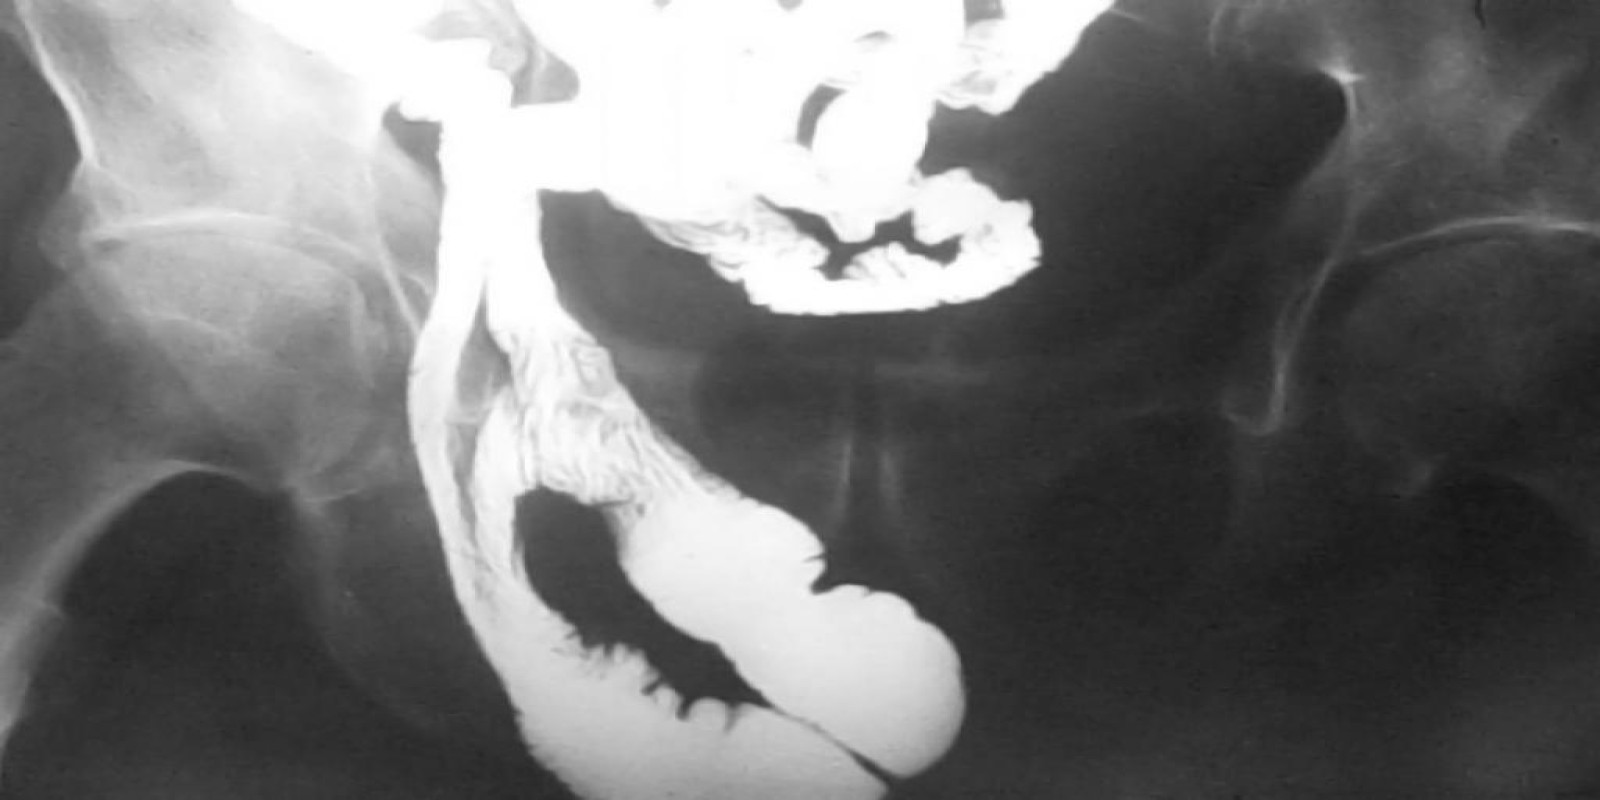

Caso Código 103A de Hérnia Inguinal

Cod.: 103A